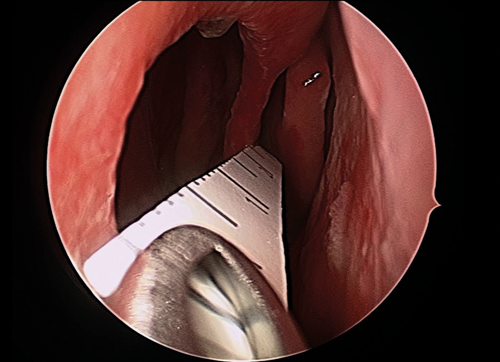

The procedure is performed under general anaesthesia and by using a 4mm 0° scope. Initially, the perforation size is measured by using a soft ruler (see Figure 1). Cottonoid pledgets embedded in 1% rupivicaine and adrenaline (1:2000) are placed bilaterally in the nasal cavity for topical vasoconstriction. The mucosa around the perforation, the floor of the nasal cavity and the nasal lateral wall, from where the flap is raised, are infiltrated with 1% rupivicaine and adrenaline (1:100.000).

Figure 1. Endoscopic view of a soft ruler measuring the size of the nasal septal perforation.